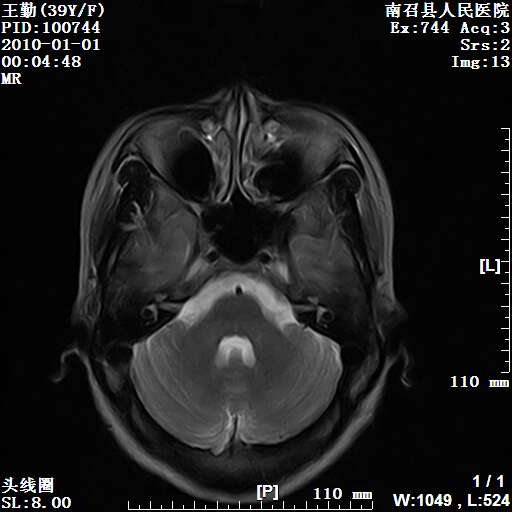

以下是引用随光逐影在2010-1-22 9:03:00的发言:[br]考虑左侧中颅窝(蝶骨翼区)脑膜瘤侵犯蝶骨翼并突入左侧眼眶。

以下是引用水过无痕在2010-1-22 14:55:00的发言:[br]一、定位:颅外占位;二、定性:恶性可能性大;三、组织来源:来源于左侧眼外直肌或其他部位;考虑为:横纹肌肉瘤>转移瘤>脑膜瘤.